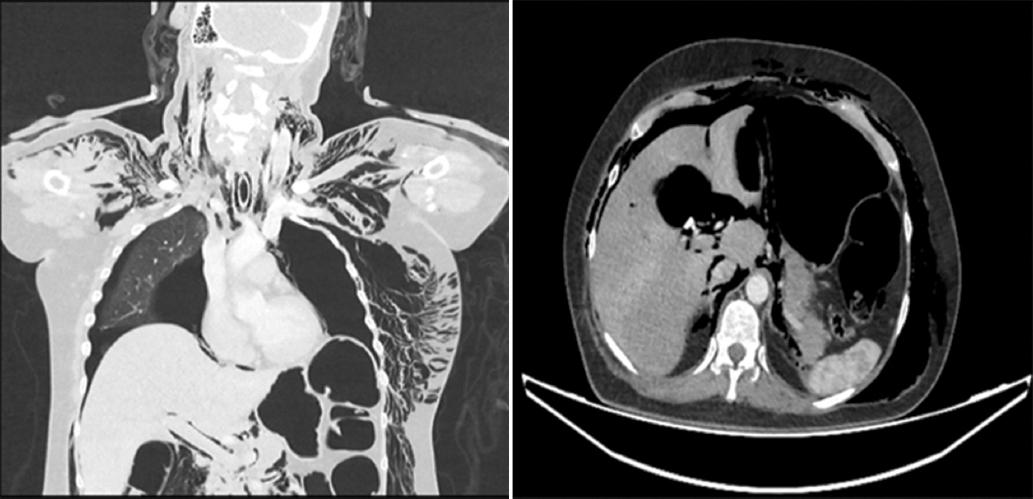

Mujer de 55 años de edad con antecedente de diabetes mellitus y dislipidemia, colecistectomía 2 años antes. Enviada por hallazgo incidental de coledocolitiasis múltiple en ultrasonido abdominal confirmada con colangioresonancia magnética evidenciando dilatación de via biliar extrahepática de 14 mm y 6 litros de hasta 9 mm en colédoco. Ingresa a procedimiento de CPRE bajo intubación orotraqueal iniciando canulación con esfinterotomo y guia 0.035” teniendo más de 3 accesos al conducto pancreático ocurriendo migración de porción hidrofílica distal de guía 0. 035” al conducto pancreático dorsal. Se logró acceso al conducto biliar evidenciando en la colangiografía dilatación de la vía biliar extrahepática y múltiples litos en colédoco. Se realizó esfinterotomía sin eventualidad aparente y posteriormente barridos con balón biliar extrayendo 6 litos. Durante el procedimiento ocurrió desaturación hasta 20% a pesar de manejo avanzado de la vía aérea por lo que fue reintubada tras múltiples intentos reiniciando CPRE canulando conducto pancreático y logrando extracción de cuerpo extraño (porción hidrofílica de guía 0.035”) en región distal de páncreas con ayuda de canastilla biliar colocando prótesis pancreática de 7 french x 5 cm. Al término del procedimiento se apreció enfisema subcutáneo masivo que afectaba región periorbitaria, cuello, tórax, abdomen y región proximal de miembros pélvicos. Se introdujo gastroscopio no apreciando perforación de duodeno. En control fluoroscópico se evidenció fuga de material de contraste a retroperitoneo sugestivo de perforación tipo 2 de Stapfer (Fig. 1) Ante la presencia de enfisema masivo y reintubación dificil se sospecha lesión traqueal. Se realizó tomografía contrastada de cuello, tórax y abdomen identificando enfisema subcutáneo con compromiso facial, orbitario, cuello, tórax, abdomen, miembros pélvicos, así como neumotórax, neumomediastino y neumoperitoneo. Se evaluó por el servicio de cirugía de cabeza y cuello sin evidenciar disrupción traqueal ni lesión en vía aérea (Fig. 2). Se ingresó a unidad de cuidados intensivos colocando sondas endopleurales de forma bilateral. Fue documentada elevación de amilasa y lipasa mayor a 1500 UI/L catalogándose como pancreatitis post CPRE. Ante inestabilidad hemodinámica con necesidad de escalar apoyo aminérgico sin respuesta se realizó laparotomía exploradora encontrando hematoma retroperitoneal no expansivo de 10 x 10 cm. No se identificó sitio de perforación duodenal. Se colocó penrose en cara posterior del duodeno, obteniendo 50 cc de líquido peritoneal con análisis del citoquímico y citológico cumpliendo criterios para peritonitis bacteriana secundaria. Paciente cursa con evolución tórpida con sepsis abdominal y falla multiorgánica falleciendo 48 horas posteriores a la CPRE.

El desarrollo de neumomediastino amerita evaluación del tracto aereo y digestivo con revisión de la integridad de la vía aérea14. En el caso presentado se realizó revisión con gastroscopio sin apreciar defectos en la pared esofágica, gástrica o duodenal descartando perforación tipo 1. Inicialmente se sospechó de una posible lesión de vía aérea como causa del enfisema. Sin embargo, en la evaluación realizada posteriormente no fue documentada lesión traqueal ni de vía aérea16,17.